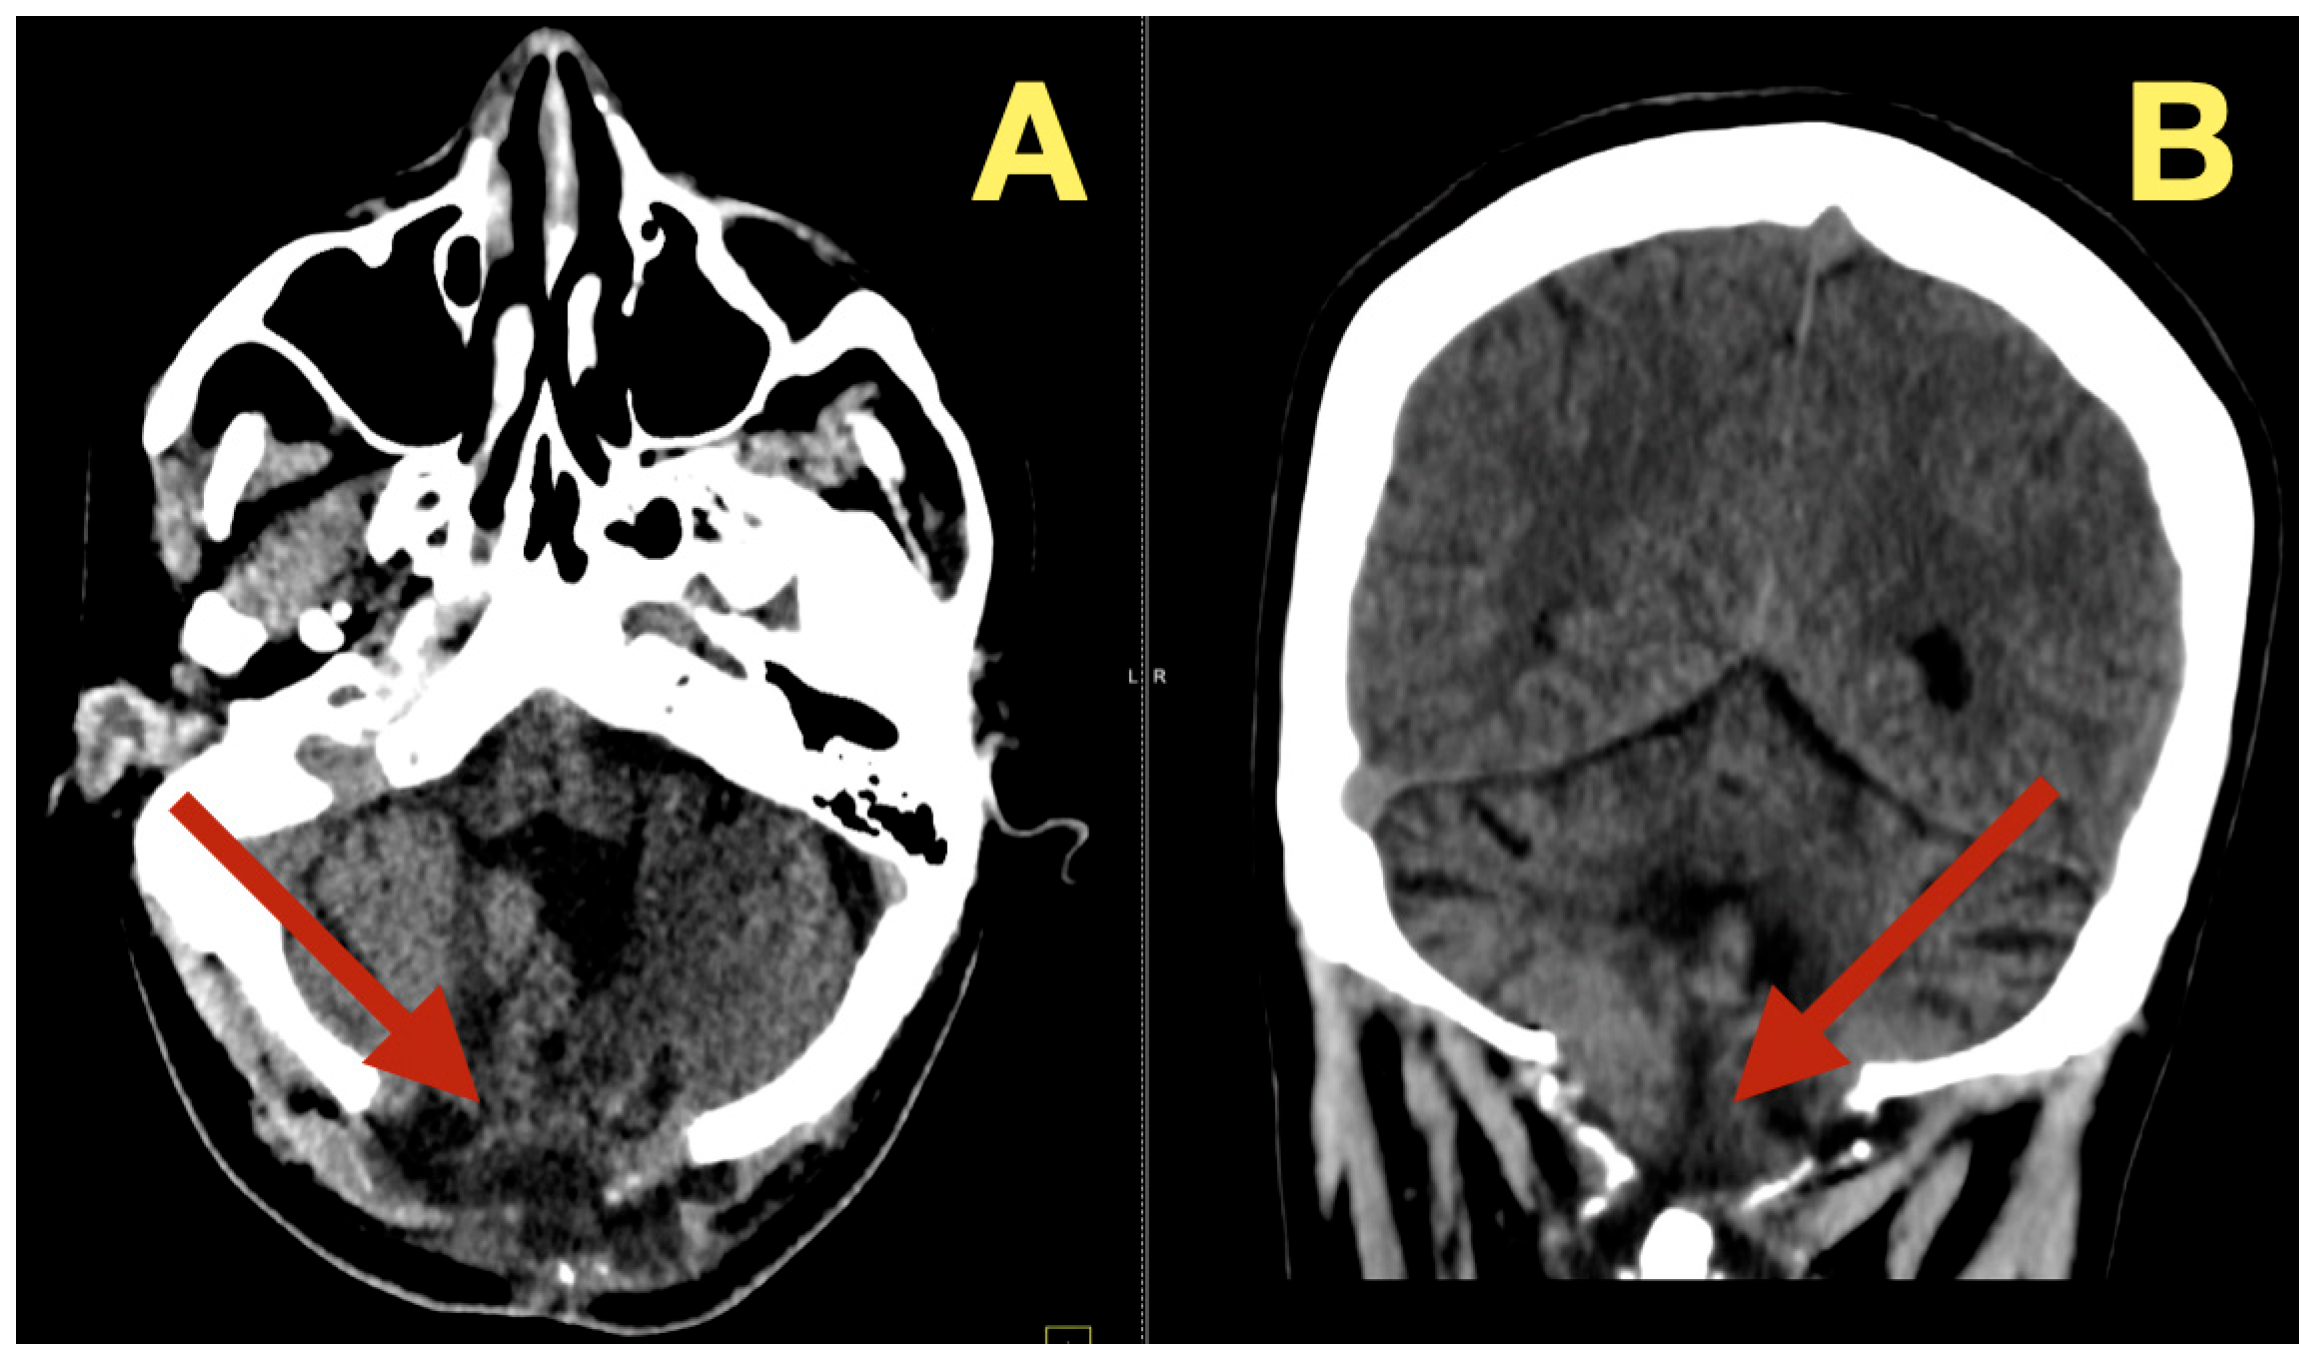

The preoperative MRI demonstrated a multilobulated mass within the fourth ventricle which was molded to the roof and cavity of the fourth ventricle. The mass arose from the inferior portion of the vermis and draped over the superior medullary velum and had smooth interfaces with the surrounding parenchyma which it displaced but did not invade. The mass was uniformly hypointense on T1 images; however, on T2/FLAIR images, the mass had hyperintensity with internal lobulation. The mass marginally compressed the uvula and nodulus and compressed the posterior surface of the pontine-medullary tegmentum. The foramen of Magendie was obliterated and both foramina of Luschka were narrowed resulting in an upstream flow void in the ventricles and a rim of periventricular interstitial edema. This created the hydrodynamic environment responsible for the patient’s symptoms. The worsening headache and vomiting in the morning, the papilledema, and nuchal rigidity resulted from the hydrodynamic environment. The avascular nature of the mass and the CSF conforming surface of the mass, as well as its central location, strongly suggested the possibility of an epidermoid cyst vs. a vascular neoplasm. The image-symptom correlation was excellent: the axial ataxia and titubation were due to compression of the fastigial nucleus and the vermian midline; the gaze-evoked nystagmus was due to disruption of the flocculonodular circuitry along the fourth ventricular roof; and the intracranial hypertension was due to obstruction of the caudal apertures. The morphology and epicenter of the mass were most consistent with a posterior fossa midline epidermoid tumor of Type 2 (fourth-ventricle epicenter) with a dominant relationship to the tela choroidea and cerebellomedullary fissure, anticipating a roof-centered growth pattern and possible focal adherence to the ventricular floor.

On the axial post contrast T1 plane (Figure 1A), the mass occupied the ventricular space like a mold, did not enhance, and was in the midline. The medial surface of the mass was in contact with the cerebellar vermis and the lateral surface of the mass slightly indented the tonsillar surfaces without penetrating into the parenchyma. On the mid sagittal T1 view (Figure 1B), the mass was in contact with the inferior vermis and caused an upward bowing of the superior medullary velum and flattening of the dorsal medulla and this explained the patient’s episodes of pressure-induced vomiting by mechanical stimulation of the area postrema. The coronal T1 reconstruction (Figure 1C) clearly demonstrated that the mass was in the midline and caused an equal compression of the two outlet recesses and was consistent with the absence of laterality in the patient’s deficits. On T2 (Figure 1D) and mid sagittal FLAIR (Figure 1E), the mass’ fluid-like appearance and internal lobulation were prominent; the surface of the mass was molded to the fourth ventricular CSF and not invading the fourth ventricular CSF, and this was a classic finding for this type of mass and accounted for the unusual severity of the fastigial/vermian hub being compressed and not destroyed.

Figure 1.

Preoperative MRI of the posterior fossa. (A): Axial post-contrast T1: non-enhancing, lobulated mass centered in the fourth ventricle (arrow). (B): Mid-sagittal T1: inferior-vermis contact with upward bowing of the superior medullary velum and dorsal brainstem compression (arrow). (C): Coronal T1: strict midline localization with symmetric crowding of the ventricular outlets (arrow). (D): Axial T2: intrinsically high signal with molded margins against cerebellar tonsils (arrow). (E): Mid-sagittal FLAIR: high signal lesion with effacement of Magendie and narrowing of Luschka, concordant with obstructive hydrocephalus (arrow). Radioclinical correlation: vermian compression → truncal ataxia/titubation; flocculonodular disturbance → gaze-evoked nystagmus; outlet occlusion → intracranial hypertension.